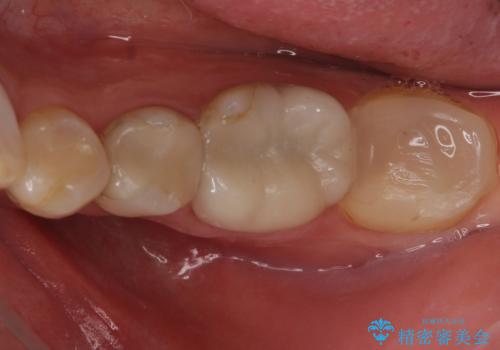

クラウンでは歯のがたつきを修正することもできます。

虫歯の除去と歯の捻転の両方を解決することができました。